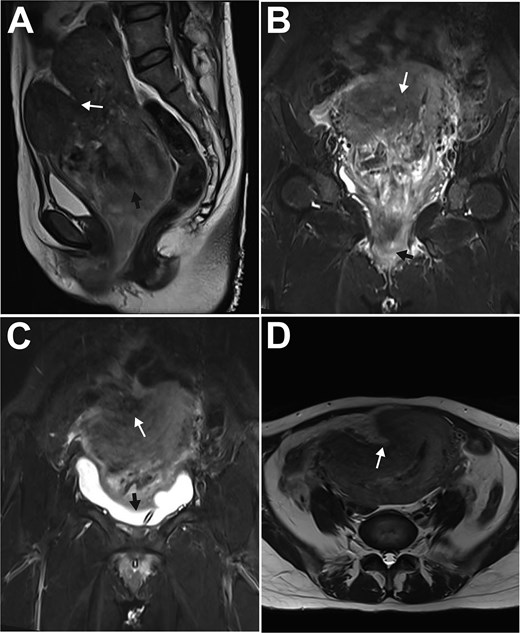

At laparotomy, the uterus was sized at 12 weeks with a 2.5 × 4 cm depression on the right anterofundal wall (Fig. 2A). Following an unsuccessful transvaginal reduction, a uterine incision was made over the depression, exposing and enucleating a 9 cm submucosal myoma (Fig. 2B). The myoma bed was sutured, and minimal endometrial bleeding was controlled with intrauterine balloon tamponade alongside pelvic drain placement. Postoperative recovery with antibiotics, uterotonics, and anemia correction was uneventful. The balloon was removed the next day, and the patient was discharged on postoperative day 7. Pathology confirmed uterine leiomyoma with vascular changes in the main mass and infarction in the introital specimen. A follow-up ultrasound on day 15 was normal.

Intraoperative findings during laparotomy for uterine inversion. A: Enlarged uterus with smooth serosa; a 2.5 cm-diameter, 4 cm-deep distinct depression (white arrow) on the right anterofundal wall; B: Surgically enucleated, bisected uterine myoma, showing typical leiomyoma gross features: Dark red color, soft consistency, whorled cut surface.